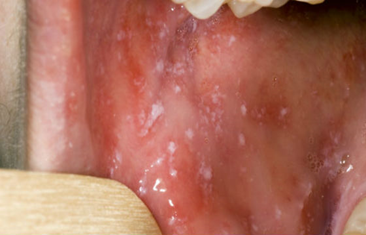

Пятна Бельского—Филатова—Коплика

Для заболевания характерна везикулезная сыпь,  может располагаться на любых участках кожи, в. ч. волосистой части головы, слизистые оболочки полости рта, половых органов. Стадия развития сыпи такие же, как при герпетической инфекции (пятно—папула—везикула—корка); везикулы однокамерные, часто имеют пупковидное вдавление в центре.